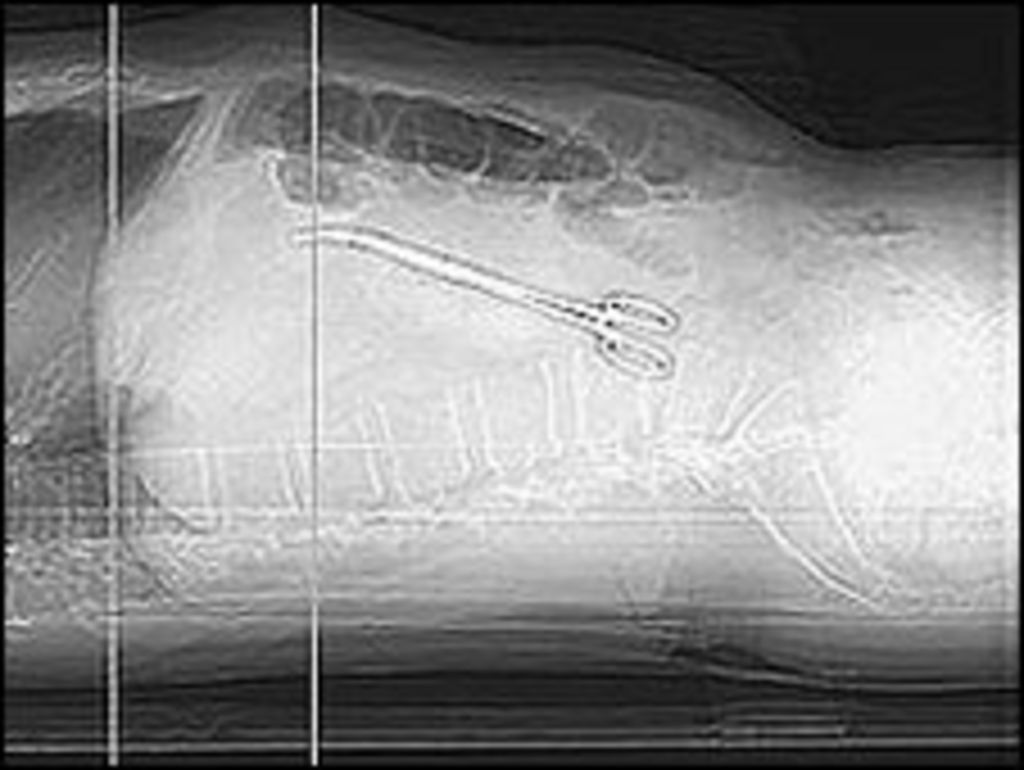

Figure 1 from A case of surgical instrument left in the abdomen and Surgical Tools Left In Patients patients with cases were those in whom instruments or sponges had been left after a surgical procedure; the term retained surgical item refers to any surgical sponge, instrument, tool, or device that is. retained surgical item (rsi) is now the preferred term (rather than retained foreign body or object) because foreign. we present a case of. Surgical Tools Left In Patients.